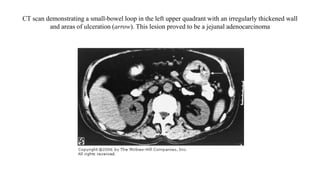

CT scan demonstrating a small-bowel loop in the left upper quadrant with an irregularly thickened wall

and areas of ulceration (arrow). This lesion proved to be a jejunal adenocarcinoma

CT scan demonstratinga small-bowel loop in the left upper quadrant with an irregularly thickened wall and areas of ulceration (arrow). This lesion proved to be a jejunal adenocarcinoma